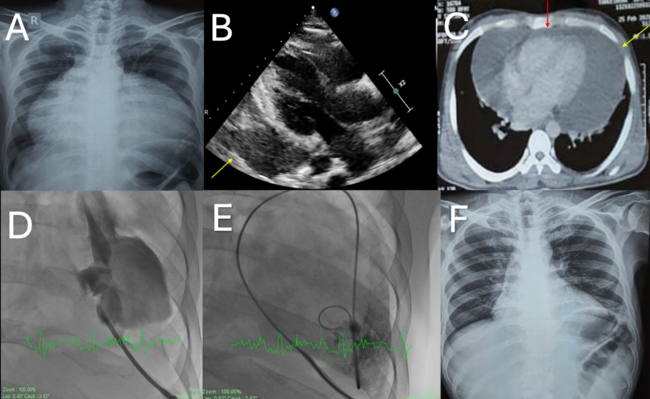

Physical examination revealed a heart rate of 110 beats per minute and a blood pressure of 88/56 mm Hg. Cardiovascular examination was significant for an elevated jugular venous pressure, an untraceable point of apical impulse, and muffled heart sounds. Initial bedside chest radiography (Figure A) revealed apparent cardiac enlargement with a money-bag appearance, suggesting a possible pericardial effusion. Urgent bedside 2-dimensional (2D) echocardiography demonstrated a large loculated pericardial effusion with a diameter of 4.5 cm lateral to the left ventricle, with features suggestive of early tamponade. The effusion appeared brightly echogenic and loculated around the left ventricle, suggestive of pyopericardium (Figure B [yellow arrow], Video 1). Computed tomography of the chest showed thick pericardial effusion predominately lateral to the left ventricle and along the right atrium, with minimal effusion anterior to the right ventricle (Figure C). Additionally, access for pericardiocentesis appeared possible only through the left ventricular apex.

The patient was taken for emergency pericardiocentesis, and, following transapical pericardial sheath placement, a contrast injection confirmed a loculated pericardial effusion around the left ventricular apex (Figure D, Video 2). We had difficulty in aspiration by a 6F pigtail and, owing to the purulent nature and near complete loculation, intrapericardial thrombolysis to facilitate pericardiocentesis was considered (Figure E, Video 3). The patient successfully underwent transapical pericardiocentesis facilitated by 10 mg of intrapericardial tenecteplase instillation, which yielded 800 mL of thick purulent pericardial fluid. Laboratory analysis of the pericardial fluid revealed a rich lymphocytic exudate and grossly elevated adenosine deaminase levels.

Loculated pericardial effusions are often seen in patients with infectious causes of pericarditis due to the presence of densely fibrinous strands in the exudate. This may sometimes necessitate nonconventional therapeutic measures such as unusual access routes (in this case a transapical route) and intracavitary thrombolytic agents to facilitate adhesiolysis for complete drainage. A 2D transthoracic echocardiogram prior to discharge revealed complete resolution of the pericardial effusion with no evidence of pericardial constriction (Video 4). The patient subsequently improved and did well on oral antitubercular and antiretroviral. Follow-up chest radiograph after 8 weeks showed complete resolution of the pericardial effusion (Figure F).